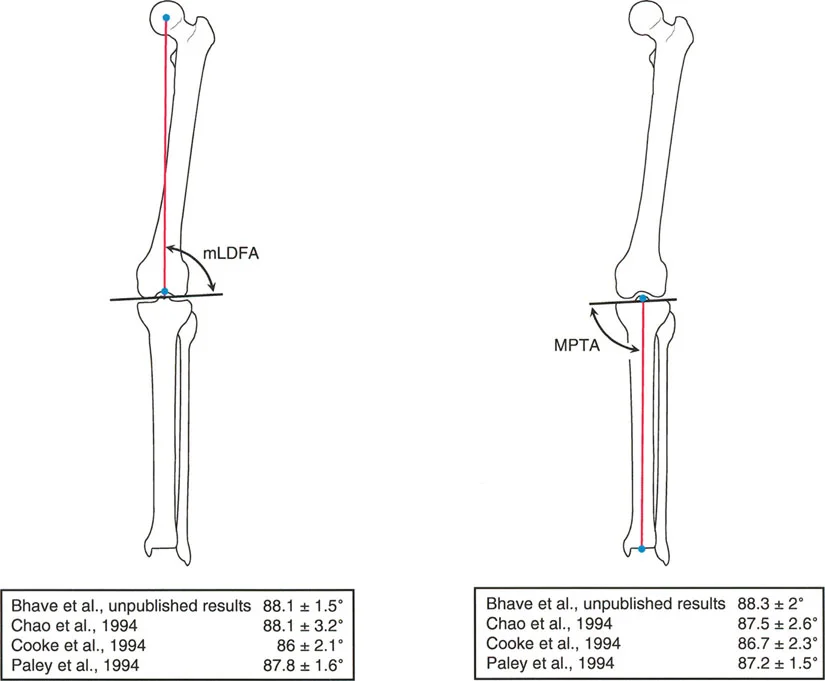

الزاوية الفخذية البعيدة الوحشية الميكانيكية (mLDFA)

هي الزاوية الوحشية (الخارجية) المتكونة بين المحور الميكانيكي لعظم الفخذ وخط مفصل الفخذ البعيد (خط مماس لأبعد نقطتين في لقمتي الفخذ الإنسية والوحشية).

* القيمة الطبيعية المقبولة لـ mLDFA هي 87.5 درجة ± 2 درجة.

* ملاحظة سريرية: عظم الفخذ البعيد يكون عادةً في درجة طفيفة من الفحج بالنسبة لمحوره الميكانيكي.

الزاوية الظنبوبية القريبة الإنسية الميكانيكية (MPTA)

هي الزاوية الإنسية (الداخلية) المتكونة بين المحور الميكانيكي لعظم الساق وخط مفصل الساق القريب (خط يمر عبر العظم تحت الغضروفي للسطح العلوي لعظم الساق).

* القيمة الطبيعية المقبولة لـ MPTA هي 87 درجة ± 2 درجة.

* ملاحظة سريرية: عظم الساق القريب يكون عادةً في درجة طفيفة من التقوس بالنسبة لمحوره الميكانيكي.